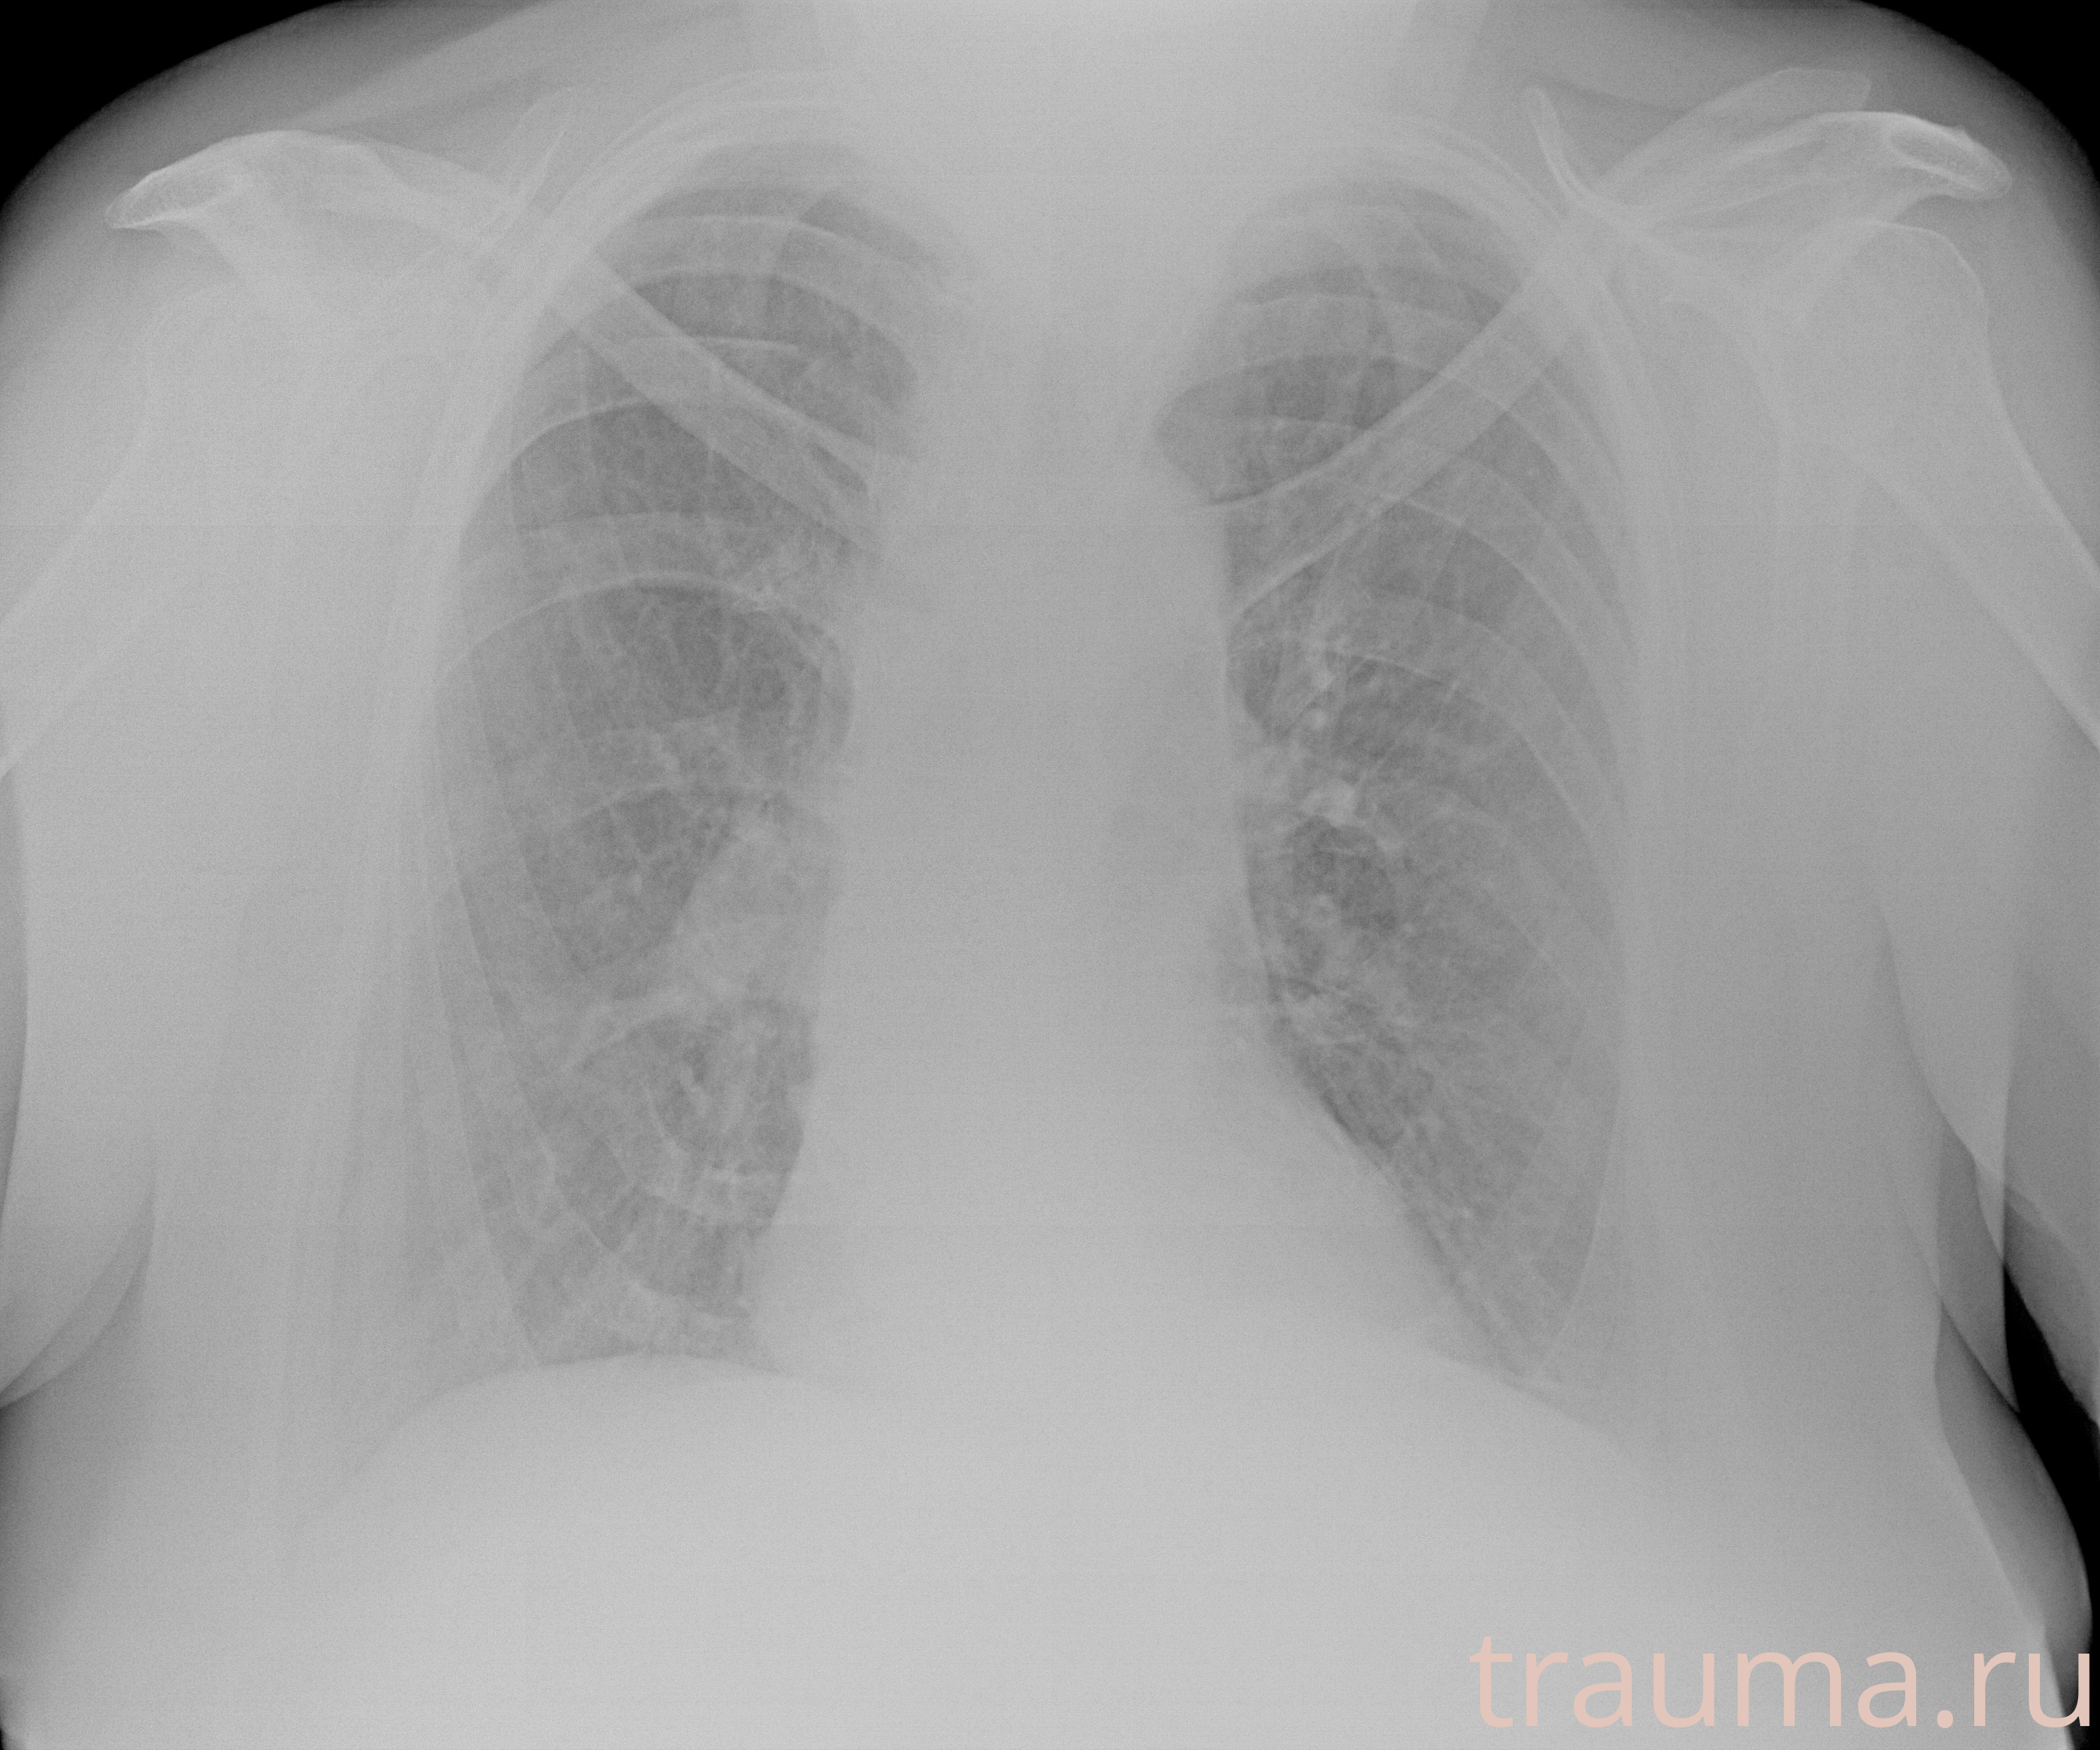

Рентгенограммы

Рентген на дому: по вашему адресу приезжает врач-рентгенолог, травматолог-ортопед с мобильным рентгеновским аппаратом, проводит диагностику травмы или заболевания, делает необходимые рентгенограммы, дает рекомендации по дальнейшему лечению. Получить качественные снимки в домашних условиях возможно благодаря уникальной методике, разработанной МосРентген Центром для института  Склифосовского

Яркость: 1   Контраст: 1   Инвертировать: 0 Увеличение: 1

Перетаскивайте мышь вверх/вниз для контраста, влево/право для яркости. Прокрутка колесом изменяет масштаб. Нажмите Сбросить для возврата к исходному изображению. При увеличении держите мышь в той области, которую хотите рассмотреть.

при переломе шейки бедра и пневмонии от компании МосРентген Центр - партнера Института имени Склифосовского